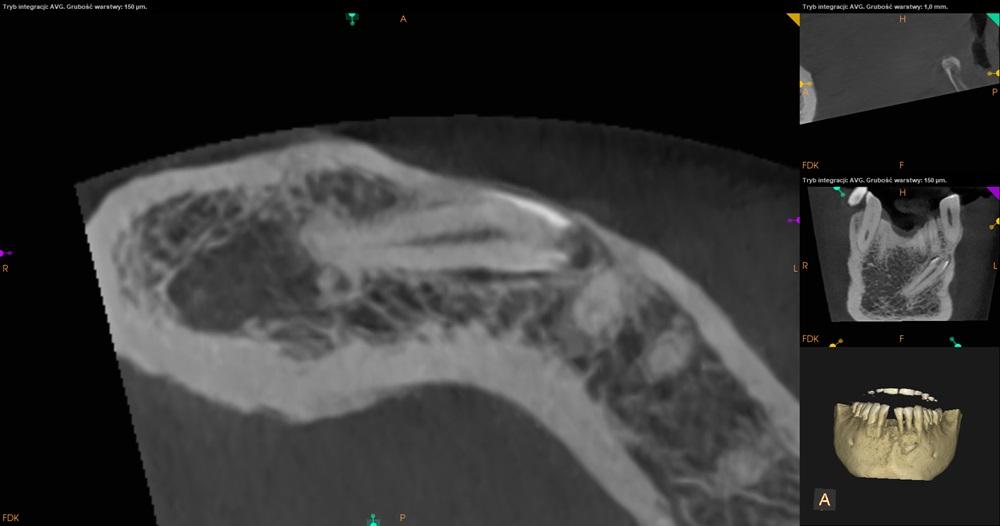

Tomografia CBCT żuchwa.

Ząb 41 – całkowicie zatrzymany. Położony skośnie, koroną skierowany w stronę mezjalną z przekroczeniem linii pośrodkowej. Korona zęba 41 położona po stronie przedsionkowej wierzchołków korzeni 33 i 32. Resorpcja korzeni niewidoczna. Wierzchołek korzenia zęba 41 lekko zagięty.